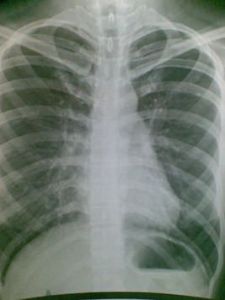

肺部鈣化點是肺結核痊癒的形式之一。正常肺組織是由肺泡、淋巴微血管、細支氣管等組成,呈粉紅色。若有相當數量和毒力強的結核桿菌侵入肺組織並在裡面生長繁殖,產生代謝產物,使肺組織受到破壞,出現好像變質的乳酪一樣的物質,使正常的結構、生理功能消失。醫學上稱為乾酪樣壞死。壞死物偏於酸性,不易液化吸收,能長期存在。在機體抵抗力強,或者化療後,乾酪樣病灶中的結核桿菌代謝低落,繁殖能力被削弱,病灶失水而乾燥,碳酸鈣和磷酸鈣沒著形成鈣化。

肺部的鈣化斑只是人體肺細胞壞死之後產生的一些特殊的變異,人體每天都在進行新陳代謝,一些細胞壞死是正常現象,壞死之後,因為自身循環不暢,從而在肺部中沉著下來,形成鈣化斑,在胸透下顯示出很像是結石的亮點。一般情況下,這種斑點在胸透檢查中只有0.5cm左右。鈣化斑如同皮膚上長的痣,只是一些壞死細胞的沉著,大多數是良性的,而且病人本身大多數都沒有什麼症狀,一般情況下不用處理。

正如資料所言,只要是0.5厘米以下,對身體沒什麼影響,如果在0.5厘米以上就要及時到大醫院就診.